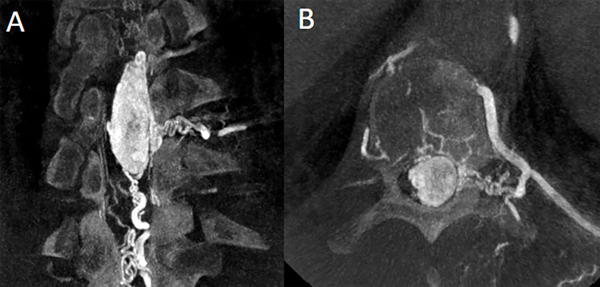

Fig 8. Caso 3. Angiografía espinal torácica: evidenciando lesión hiper vacularizada con aferencia primaria de ramo radiculomedular lateral izquierdo, de arteria intercostal. Con drenaje venoso descendente por venas perimedulares anteriores y posteriores (A y B).